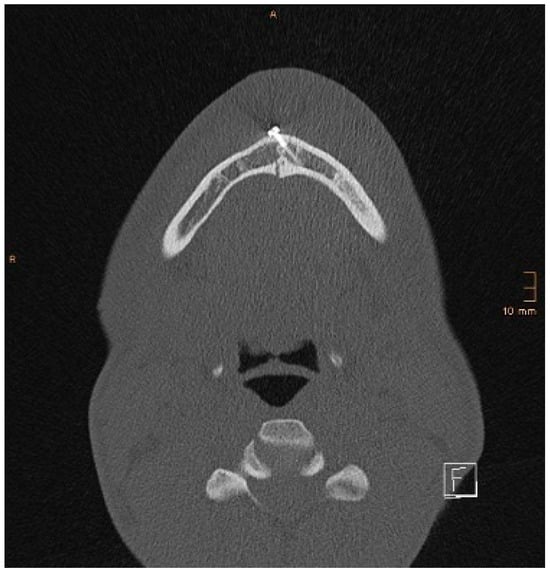

Figure 8 and Figure 9 below show another patient with a non-satisfactory reduction in the condylar neck fracture on the left-hand side due to a lingual gap present at a body fracture (Figure 8 and Figure 9).

Figure 8. Coronal CT scan showing a condylar neck angulation on the left side after ORIF. An anatomical reduction could not be achieved.

Figure 9. Axial CT scan showing the same patient as in Figure 8. A lingual gap is present after ORIF of the mandibular body fracture, contributing to the inability to reduce the condylar fracture correctly.